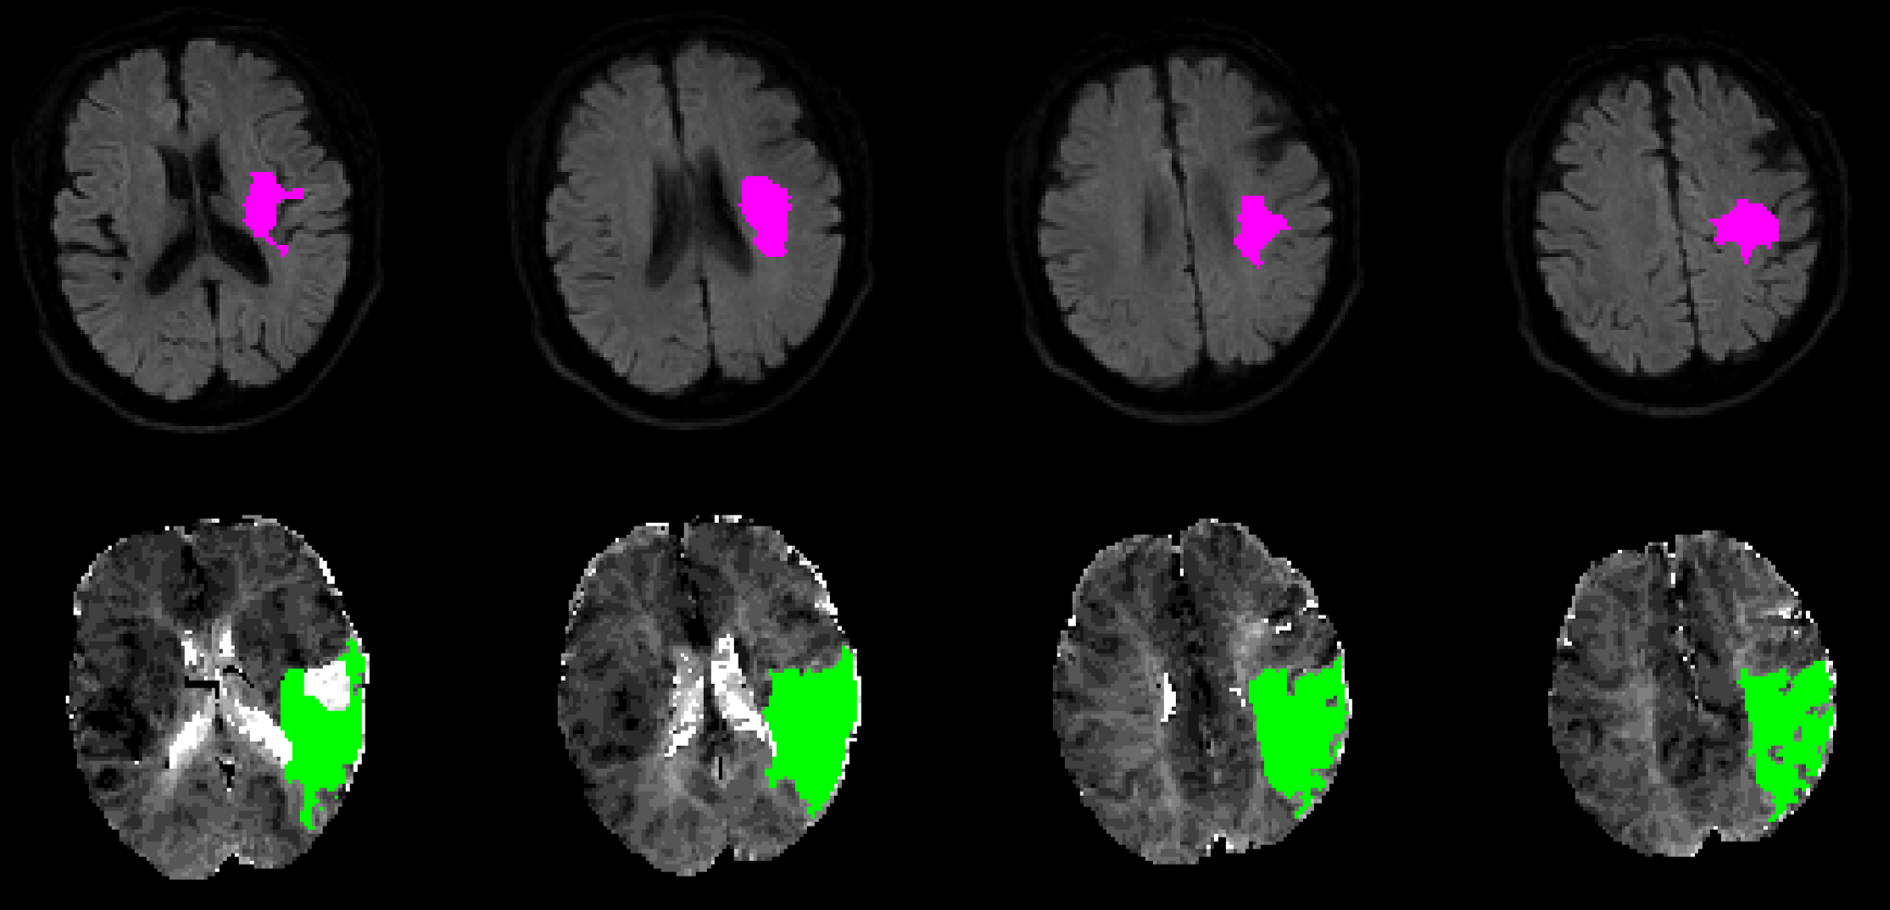

Figure 1. DWI lesion and PWI lesion automatically assessed with RApid processing of Perfusion and Diffusion (RAPID) in an AIS patient. Infarct core identified using ADC threshold (Upper row). The green regions indicate hypoperfused tissue (Bottom row). The lesion ROIs were selected by in-house MATLAB (MathWorks, Natick, MA, USA) scripts in the subsequent analysis.